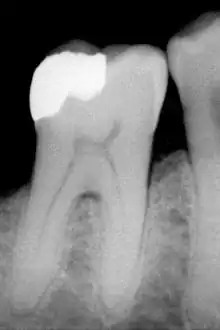

Amalgama dental

La odontología ha utilizado aleaciones de mercurio con metales como la plata, el cobre, el indio, el estaño y el zinc. La amalgama es un "material de restauración excelente y versátil"[13] y se utiliza en odontología por varias razones. Es barata y relativamente fácil de usar y manipular durante la colocación; permanece blanda durante un corto período de tiempo, por lo que puede empaquetarse para rellenar cualquier volumen irregular, y luego forma un compuesto duro. La amalgama posee una mayor longevidad en comparación con otros materiales de restauración directa, como el composite. Sin embargo, esta diferencia ha disminuido con el continuo desarrollo de las resinas compuestas.

Las amalgamas dentales modernas están hechas de dos componentes: un polvo de un compuesto de estaño-plata (Ag3Sn) y (más del 50 %) mercurio , el líquido. Durante la mezcla ("trituración"), el mercurio entra en contacto con las partículas de polvo y las partículas comienzan a dispersarse. Así, se obtiene una matriz de partículas de plata-mercurio y estaño-mercurio, con un relleno de las partículas de plata-estaño no afectadas.

Debido a que la mezcla de estaño y mercurio, la llamada fase γ2, no tiene buenas propiedades físicas (se corroe rápidamente, fuerza limitada, ...), a veces cobre se añade al polvo (o una aleación de cobre-estaño-plata, o partículas de plata-cobre añadidas a las partículas de plata-estaño). También se intentará presionar firmemente la amalgama que se ha colocado en un cavidad (odontología), para que se elimine la mayor cantidad posible de mercurio superfluo; esto se llama "condensación".